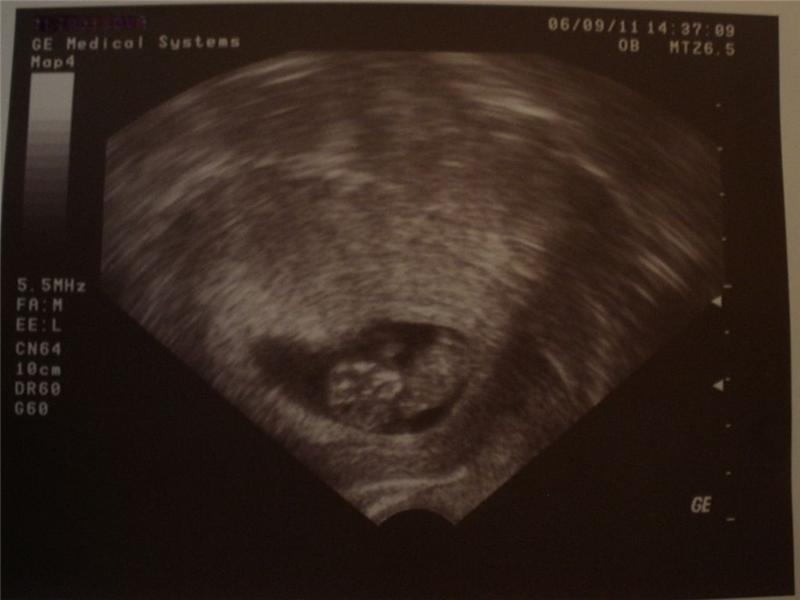

UTZ 6.9.2011 – tt. 9+6